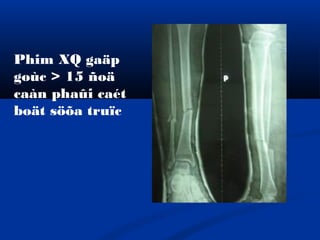

- 1.

- 3.

I. Chæ ñònh:

-Caétboät söûa truïc ñöôïc aùp duïng trong caùc tröôøng

hôïp maø sau khi naén xöông baêng boät xöông coøn bò

gaäp goùc nhieàu hôn 15 ñoä

- Boät phaûi khoâ cöùng vaø khoâng bò loûng boät